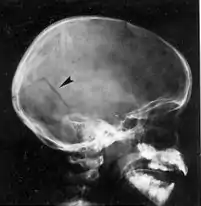

Fracturas de cráneo

A pesar de que el cráneo es una estructura ósea sólida con una gran resistencia es común que resulte fracturado si el impacto ejerce una presión excesiva sobre él,[3] ya sea por una fuerza elevada o por un área pequeña de contacto. Las fracturas de cráneo resultan de un impacto en la cabeza que por lo general es lo suficientemente grave como para provocar al menos una breve pérdida de conciencia.[15] Las fracturas de cráneo lineales son grietas sin desplazamiento de estructuras óseas a través del cráneo. Si el trauma es muy intenso puede causar un hueco o diastasis entre los bordes de la fractura. Una fractura en la cual el hueso se desplaza al interior de la cavidad craneal una distancia mayor que el grosor del hueso se llama fractura craneal desplazada.[14] La fractura craneal desplazada con fragmentos de cráneo empujados hacia la bóveda craneal es más común en un traumatismo craneoencefálico causado por un objeto con una superficie de contacto pequeña como un martillo. El tipo más común de fractura de cráneo es una fractura lineal sobre las convexidades laterales del cráneo.[15][13]

El significado clínico de las fracturas de cráneo está en relación con el daño asociado en el tejido subyacente, los vasos o nervios craneales más que a la propia fractura. Las fracturas de cráneo lineales que involucran la porción escamosa del hueso temporal pueden romper la arteria meníngea media desencadenando un hematoma epidural. Las fracturas con hundimiento del cráneo se asocian con contusiones del tejido cerebral subyacente. Si el cuero cabelludo que recubre el fragmento de cráneo con hundimiento está lacerado, el fragmento de hueso deprimido es propenso a ser contaminado con bacterias de la piel lo que puede conducir a la formación de abscesos cerebrales o encefalitis.[30] Las fracturas de la base del cráneo a menudo están asociados con la ruptura de la duramadre subyacente lo que resulta en fístulas con la fosa nasal, senos paranasales u oído. Esto que constituye una vía más de entrada de microorganismos y fugas de líquido cefalorraquídeo por la nariz o el oído.[15] Las fístulas son un conducto para la contaminación bacteriana del espacio intracraneal de la nariz, senos paranasales, o en el conducto auditivo externo.[30]

- Radiografía simple de cráneo: que es de utilidad para localizar fracturas en el cráneo que pudiesen generar un hematoma epidural, o localizar un cuerpo extraño dentro del cráneo. Suele indicarse cuando existe contusión o laceración de la piel cabelluda o herida con profundidad hasta el hueso. Tiene la ventaja de ser barata, inocua, sencilla y relativamente rápida.